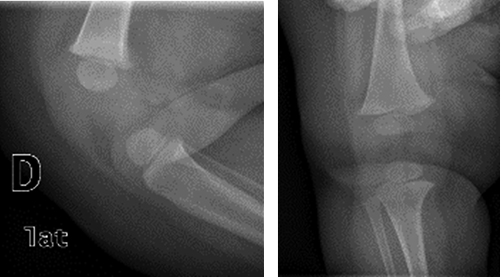

A la exploración, la rodilla derecha presentaba una marcada deformidad en hiperextensión, reducible hasta 50o de flexión (Figura 1). No se observaron alteraciones en miembro inferior izquierdo. Las maniobras de Barlow y Ortolani bilaterales fueron bilateralmente negativas. El resto de la exploración pediátrica y traumatológica resultó completamente normal.

En el estudio radiológico se observó una luxación tipo C según la clasificación de Leveuf en rodilla derecha (Figura 1). Dada la facilidad para la reducción de la luxación mediante la flexión de la misma, se inmovilizó mediante un yeso inguinopédico que se cambió la segunda semana, obteniéndose una flexión de 90o y se procedió a la retirada del mismo la cuarta semana de vida. Posteriormente se realizaron revisiones periódicas hasta el inicio de la deambulación de modo autónomo (Figura 2). Se consiguió una rodilla con función normal, con una estabilidad articular adecuada y una deambulación que además de ser satisfactoria llegó en un momento adecuado del desarrollo sicomotor de la paciente.